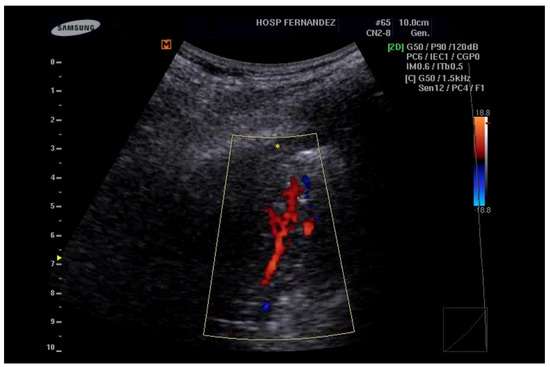

- Görg, C.; Bert, T. Transcutaneous colour Doppler sonography of lung consolidations: Review and pictorial essay. Part 1: Pathophysiologic and colour Doppler sonographic basics of pulmonary vascularity. Ultraschall Med. 2004, 25, 221–226. [Google Scholar] [CrossRef]

- Görg, C.; Bert, T. Transcutaneous colour Doppler sonography of lung consolidations: Review and pictorial essay. Part 2: Colour Doppler sonographic patterns of pulmonary consolidations. Ultraschall Med. 2004, 25, 285–291. [Google Scholar] [CrossRef] [PubMed]